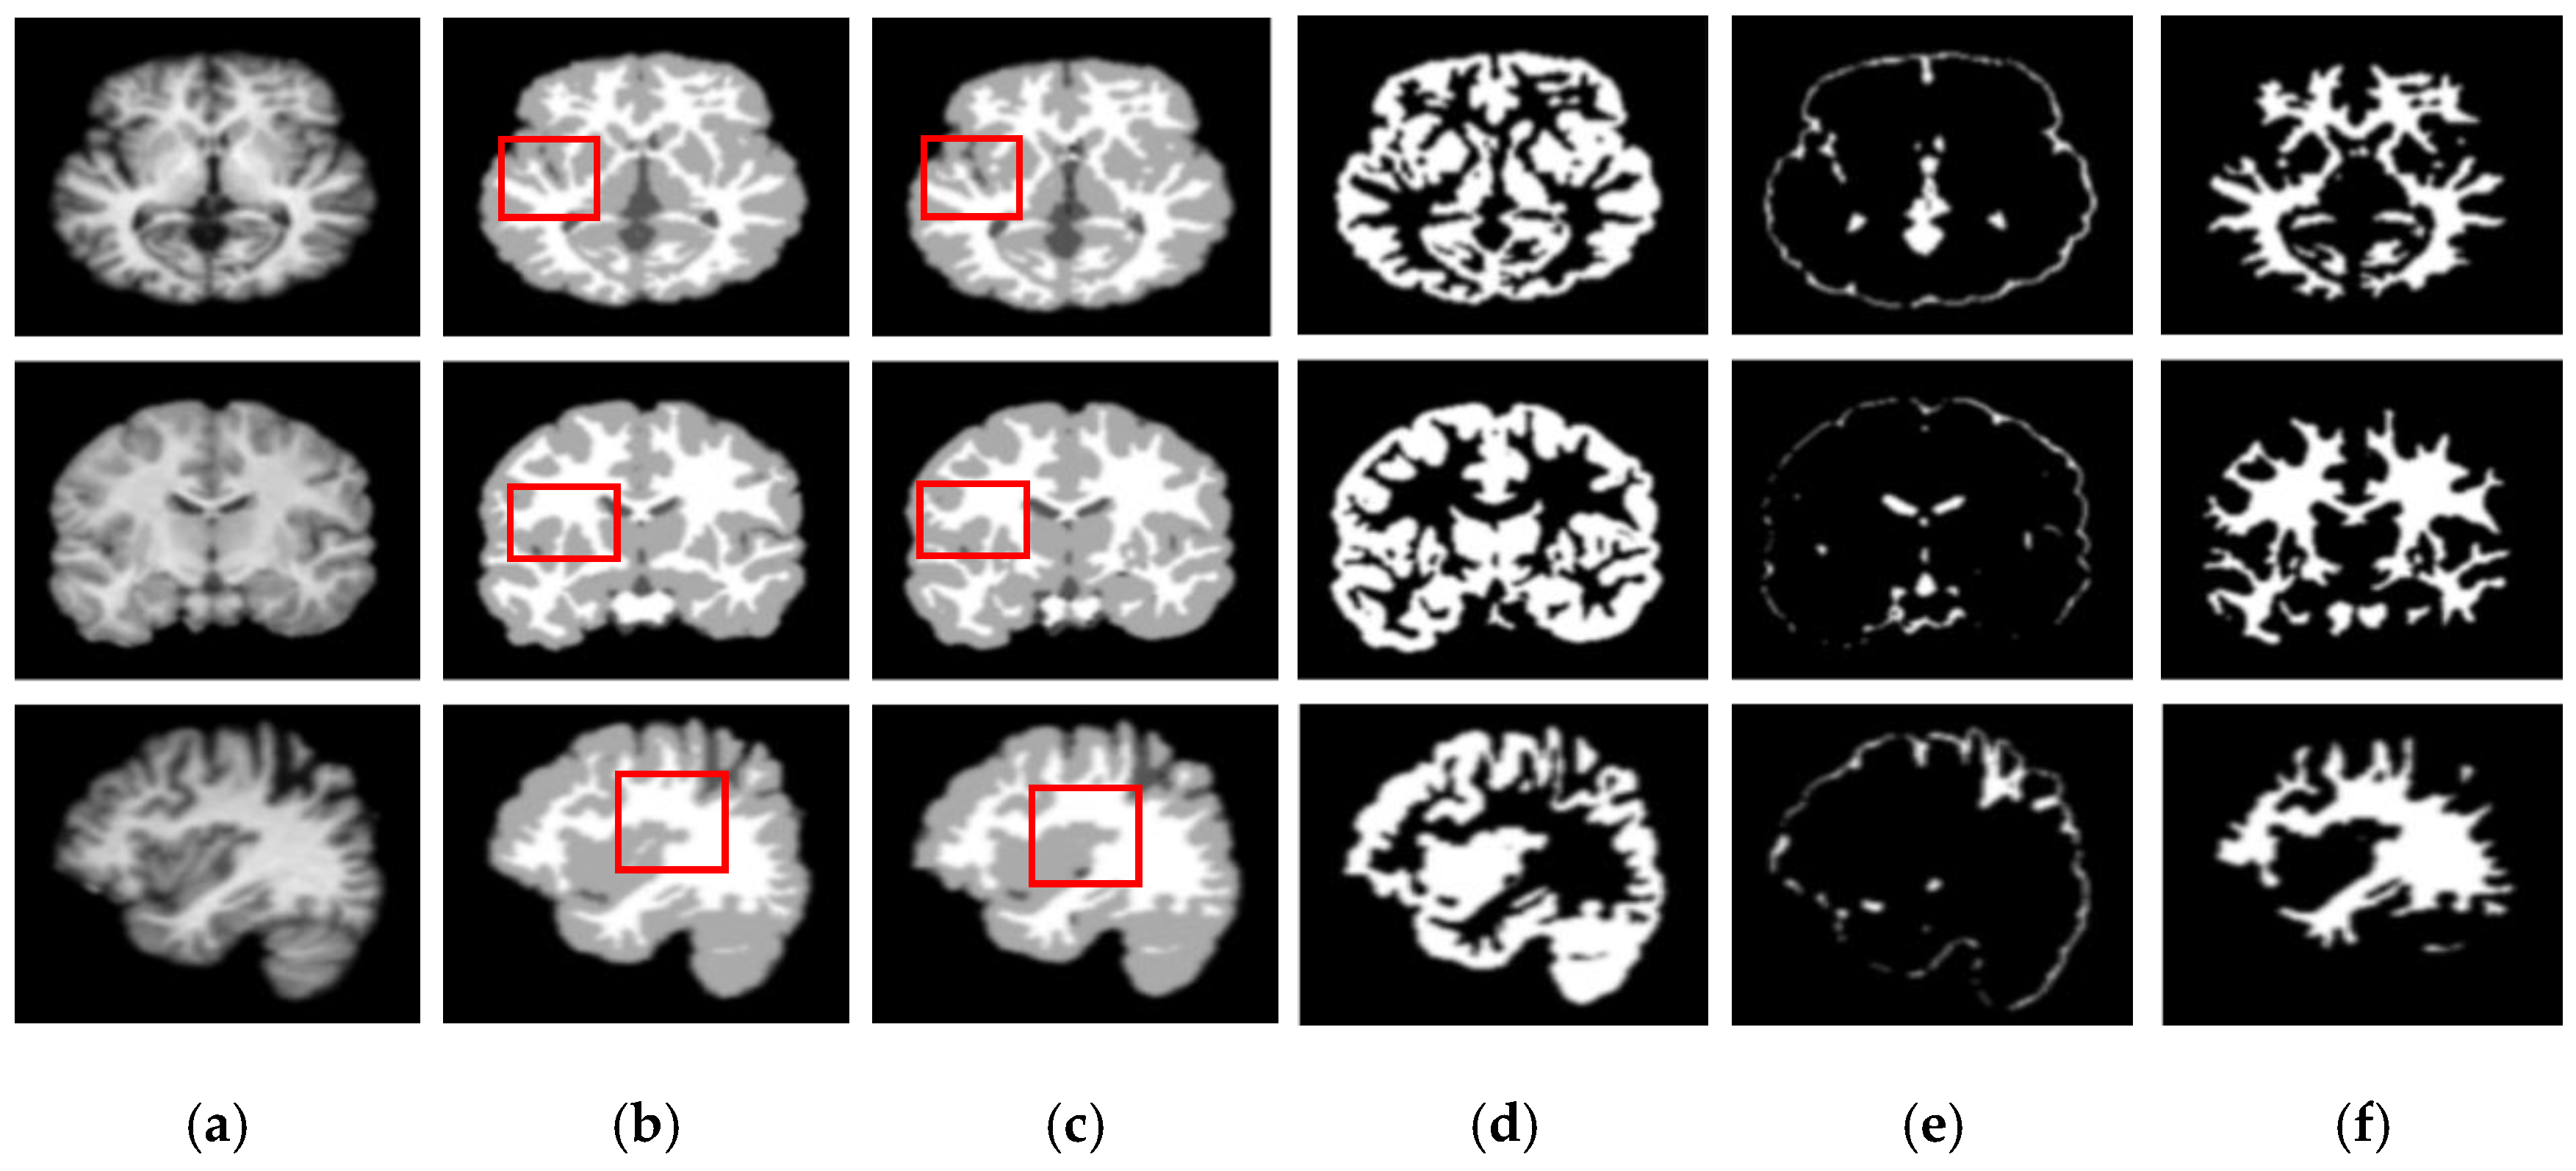

We also assessed the segmentation performance in terms of the mean square error (MSE), which is the average square difference between the original and predicted Y values. The Hausdorff distance (HD) [] was used to determine the dissimilarity between two sets in a metric space. The two sets of small Hausdorff distances are almost identical. HD and MSE are computed as listed in Table 2, where D is the Euclidean distance between two pixels, and R and C are the image height and width, respectively. To compare the segmentation results of various network architectures, we experimented on SegNet, U-net, U-SegNet, U-net++, and CE-net models under the same experimental conditions. Figure 7 and Figure 8 show comparisons of the segmentation results. As shown in Figure 7 and Figure 8, the proposed method shows superior results in terms of the quality of the segmentation map compared to those of other conventional methods. Although the skip connections in the U-net improve feature representations by combining low-level and high-level information, they suffer from a large semantic gap between low- and high-resolution feature maps, resulting in high misclassification rates of brain tissues. Furthermore, for medical images with low contrast, blurred boundaries between different tissues, the segmentation accuracies of U-net and SegNet are significantly degraded. Because the network layers in U-net++ are connected through a series of nested, dense skip pathways, leading to redundant learning of features, they did not show good performance. In particular, it can be observed that there are misclassification results in the feature maps generated by SegNet, U-net, and U-net++ in the red boxes of Figure 7c and Figure 8c. Although U-SegNet with pooling indices and skip connections yields better segmentation results, it fails to capture fine details, as shown in Figure 8c. From the highlighted red boxes in Figure 8, it can be observed that U-SegNet fails to identify differences between WM and GM tissues, and most of the GM tissues are incorrectly predicted as WM. The CE-net extracts multi-scale information through a context encoder block for the segmentation of medical images. However, the context encoder block is employed only at the bottleneck layer of the model, and thus this multi-scale information could be irrelevant by the time it reaches the final decoder layer for classification. To overcome these limitations, we extract multi-scale information at each network layer followed by the GAM to enhance the segmentation performance by directing attention to related areas. This improved segmentation can be observed in the results obtained using the proposed method. Similar results were observed for the segmentations obtained from the IBSR images, as shown in Figure 8. It can be observed that the proposed network obtains finer details than the other architectures. These results indicate that our proposed approach can strongly recover finer segmentation details while bypassing distractions between tissue boundary regions.

Figure 8.

Segmentation results for GM, CSF, and WM from brain MRI image using the existing methods and the proposed method on IBSR dataset: (a) original input image; (b) ground-truth segmentation map; (c) their segmentation results obtained SegNet, U-net, U-SegNet, U-net++,CE-net, and the proposed method (top to bottom); (d) CSF maps obtained by SegNet, U-net, U-SegNet, U-net++,CE-net, and the proposed method (top to bottom); (e) GM maps obtained by SegNet, U-net, U-SegNet, U-net++,CE-net, and the proposed method (top to bottom); (f) WM maps obtained by SegNet, U-net, U-SegNet, U-net++,CE-net, and the proposed method (top to bottom).